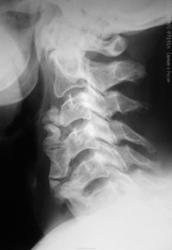

Болезнь Форестье?

Скорее нет, это не обызвествление связки, скроее аномалия развития. Ну Михайлова надо в студию...

Похоже. А вам обязательно по автору, а оссифицирующий лигаментоз не пойдет?

Пойдет, Андрей Юрьевич... Главное суть изменений...

оссифицирующий лигаментоз

+1. А какой анамнез заболевания? Травма была?

Анамнез без особенностей.